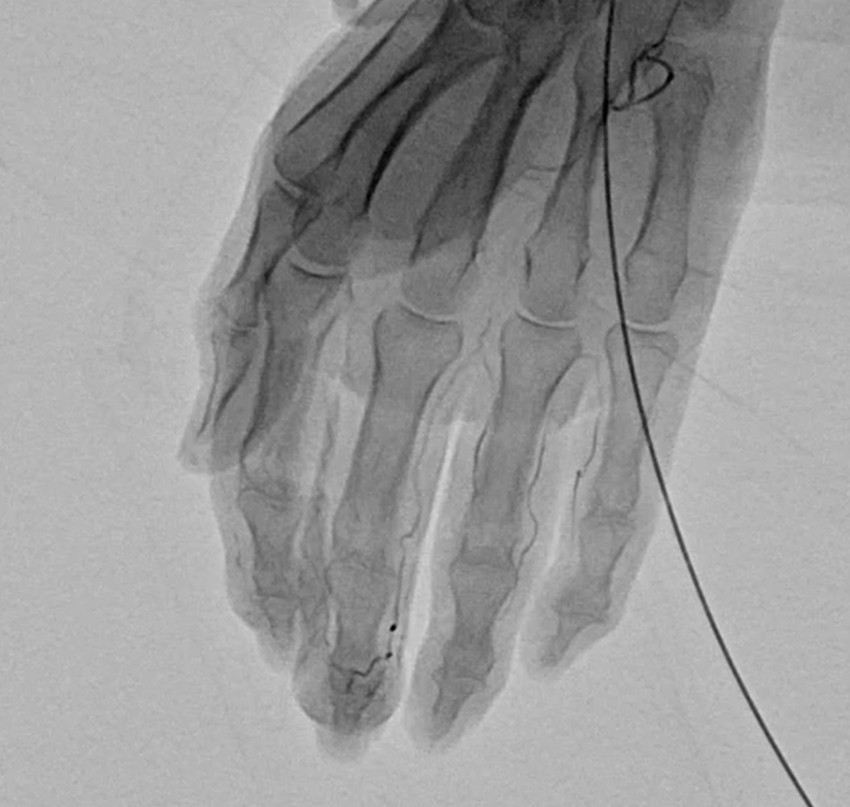

各種高度医療機器を活用した診断

やなせ整形外科では、的確に痛みなどの原因を把握して治療をするために、MRI、レントゲンはもちろんの事、エコーを使った運動器の診断を行っております。